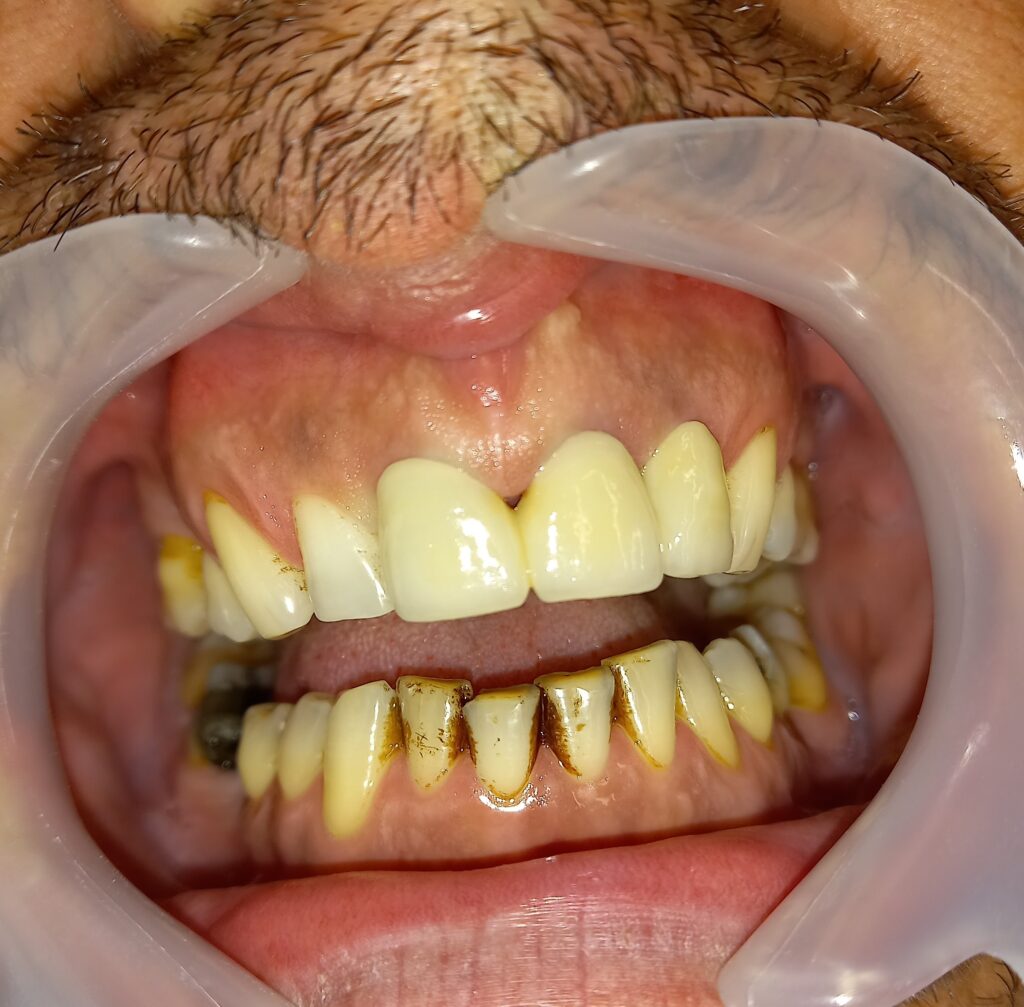

Ο ασθενής είχε μια παλιά μεταλλοκεραμική γέφυρα στην άνω πρόσθια περιοχή, την οποία θέλησε να την αντικαταστήσει με νέα προσθετική δουλειά καθώς τον ενοχλούσε πολύ αισθητικά. Μετά την αφαίρεση της παλιάς μεταλλοκεραμικής γέφυρας ακολούθησαν οι απαραίτητες οδοντιατρικές εργασίες (επανάληψη απονεύρωσης, αναδόμηση των δοντιών) στα δόντια στηρίγματα και η λήψη αποτυπώματος. Ο οδοντοτεχνίτης κατασκεύασε τη νέα ολοκεραμική γέφυρα, η οποία συγκολλήθηκε στο δόντι. Ο ασθενής είναι πλήρως ικανοποιημένος με το αισθητικό αποτέλεσμα.

ΜΕΤΑ